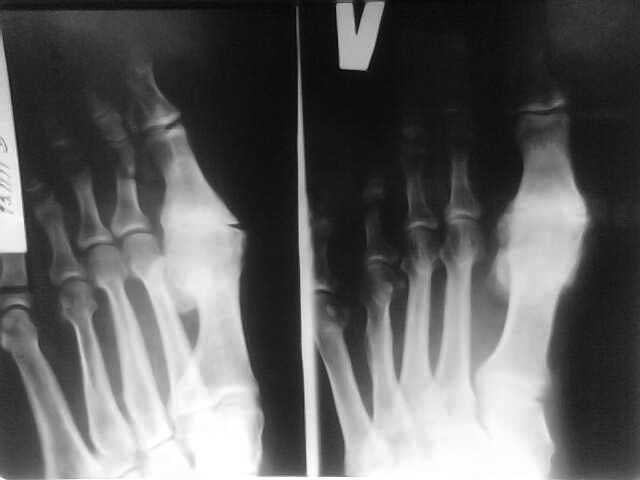

Уважаемые коллеги! Доброго времени суток. Мужчина, возраст 40 лет. Работает на себя(строитель). По характеру профессиональной деятельности часто ронял себе на ногу тяжелые предметы (радиаторы отопления, мешки с сухими смесями и т.д.)

За помощью никогда не обращался. В настоящий момент беспокоят боли в области 1 плюсне-фалангового сустава, нарушающие походку, периодические щелчки в этой области. Объективно: область 1 ПФС увеличена в объеме за счет костных разрастаний, признаков воспаления нет, омозолелая кожа на внутренней поверхности, движения в суставе качательные, б/болезненные. Хочет избавится от боли и щелчков, как можно быстрей. Извините за качество снимка- сфотографировано телефоном.

Это типичный Hallux rigidus в достаточно запущенной стадии: деформации костей, массивные костные разрастания, выраженное ограничение функции. Возможные варианты лечения - артродез или артропластика 1 ПФС.